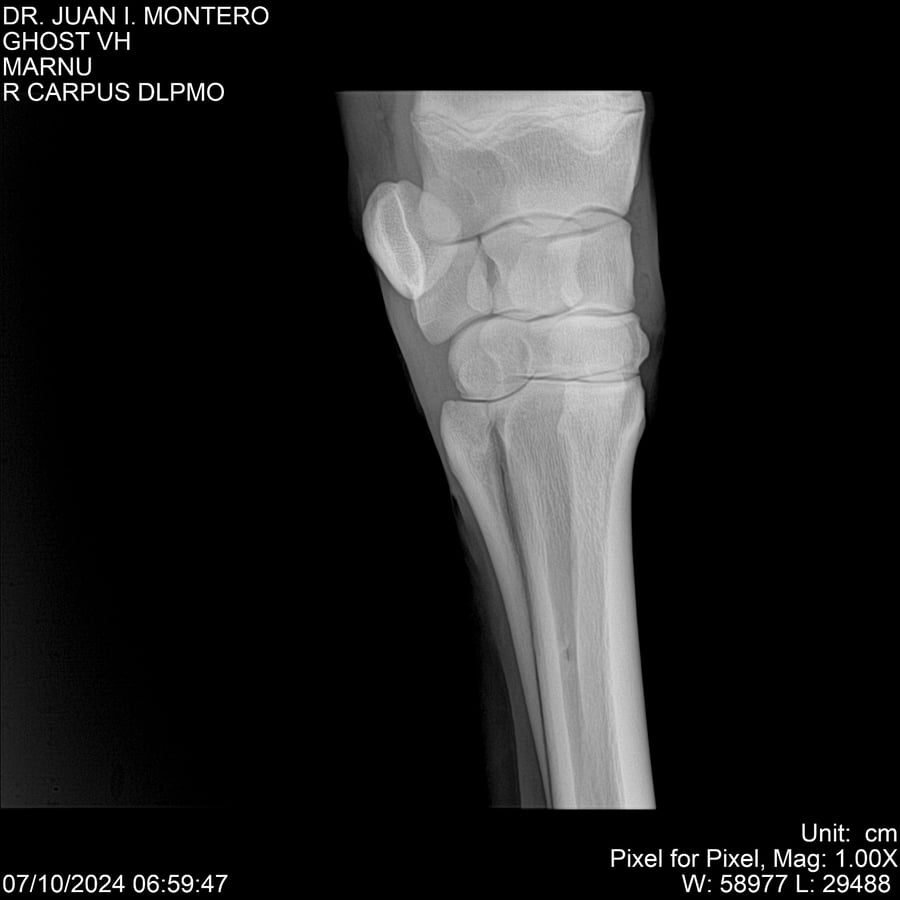

LOTE 15, GHOST VH 🔥 🔥 🔥 Lote Anterior Volver al remate Lote Siguiente Ficha Contacto Montevideo - Ficha del Lote Identificador: #282525 Categoría: Yeguarizos Montevideo - 69 Visualizaciones ClicData Contacto Empresa: Abelenda N. R., Walter Hugo Nombre*: Teléfono* : E-mail* : Mensaje Enviar Registrese gratis Este contenido Exclusivo está disponible sólo para usuarios registrados Ingresar